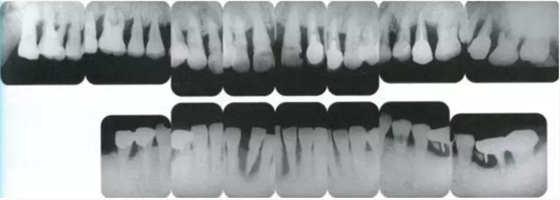

▲圖19-1

40歲,女性。來院主訴為牙齦出血,牙體晃動?;颊卟晃鼰?,因此沒有全身性問題。有明顯的牙周炎,發(fā)生了牙體移動,前牙區(qū)前突。下頜右側(cè)磨牙缺失,醫(yī)生認(rèn)為有必要進(jìn)行包括牙周修復(fù)、正畸治療、種植治療等在內(nèi)的綜合性治療。

▲圖19-4

X光片。牙槽骨明顯缺失。